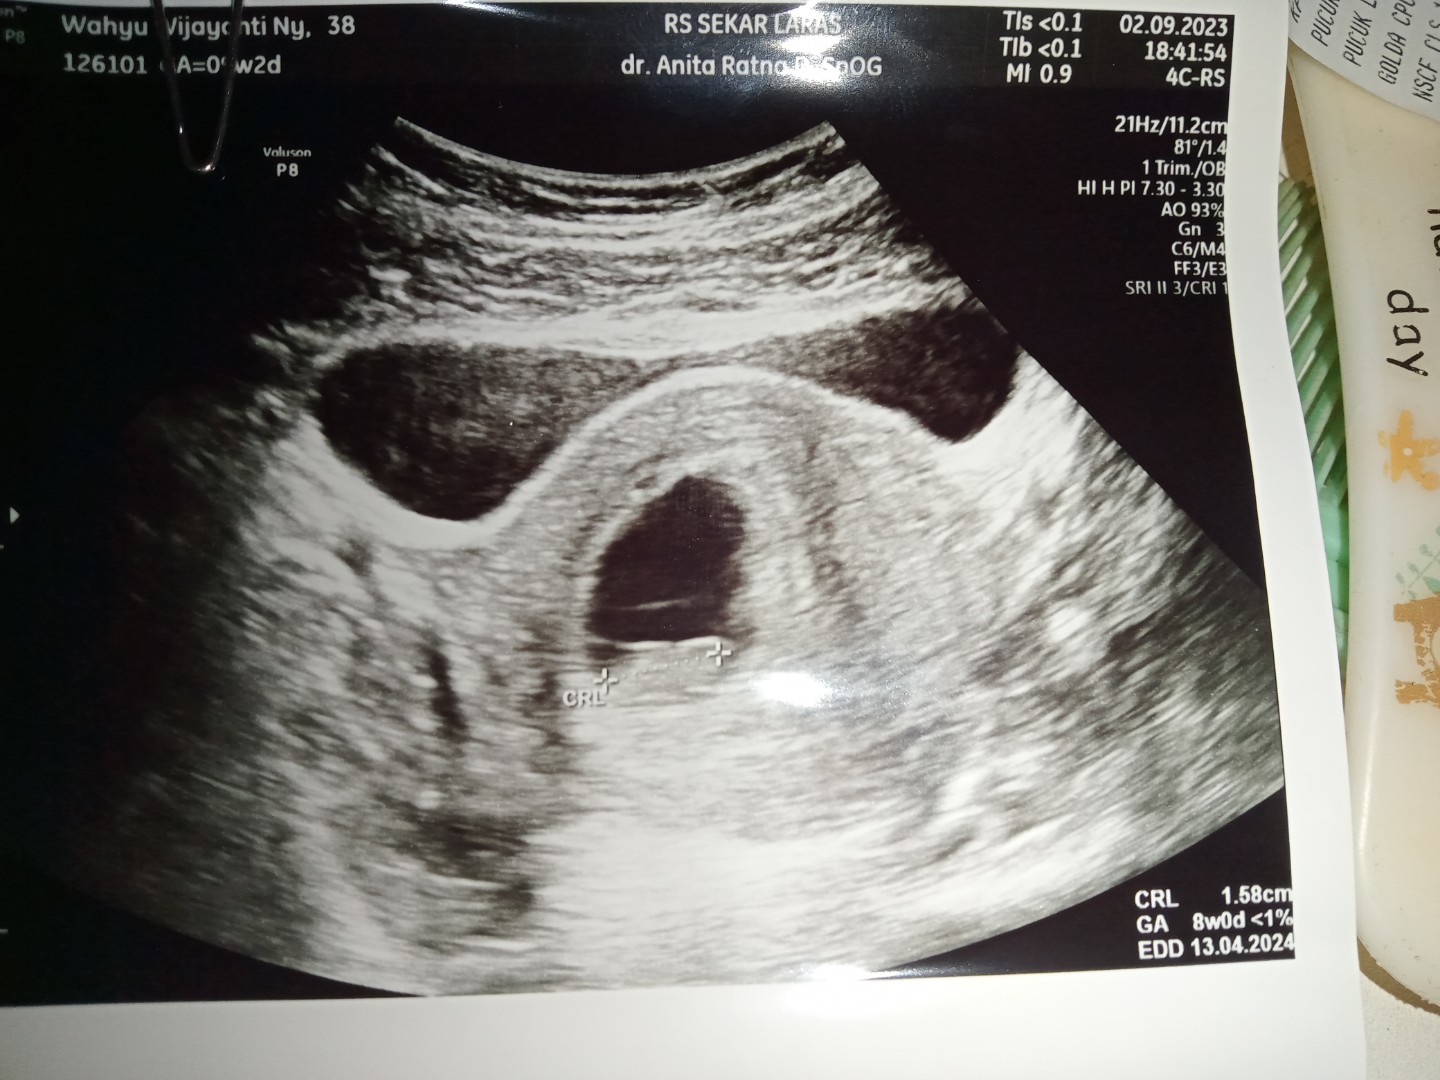

aku barusan USG Bun ini hasilnya udh ad detak jantung, riwayat SC 2 kali , hamil anak ke3... dan jarak ank ke 2 1.1 Thun hamil smbil menyusui 🙏

karena kmungkinan usia realnya blm 7 mggu bun.. saya hpht 29 Juni, hr sbtu kmrn usg, usia realnya 8 mggu, sudah tmpak janin, dan trdengar djj..

alhamdulillah kehamilan kali ini "lumayan ga rewel" utk usia saya yg 38th..tdk ada flek, msh bs utk olahraga ringan jg ..